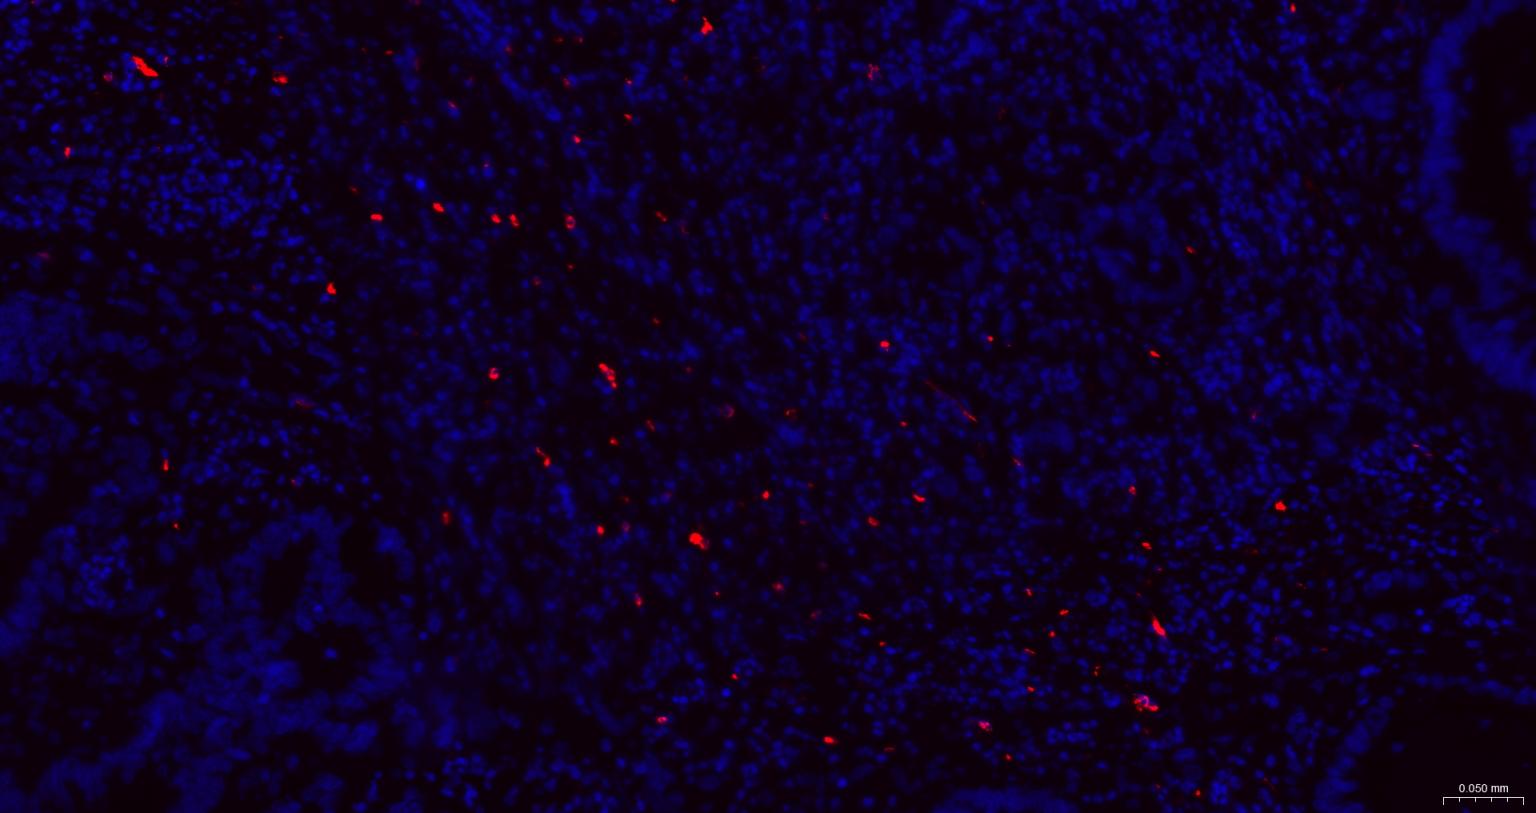

| IF | Human | 1:50-200 |